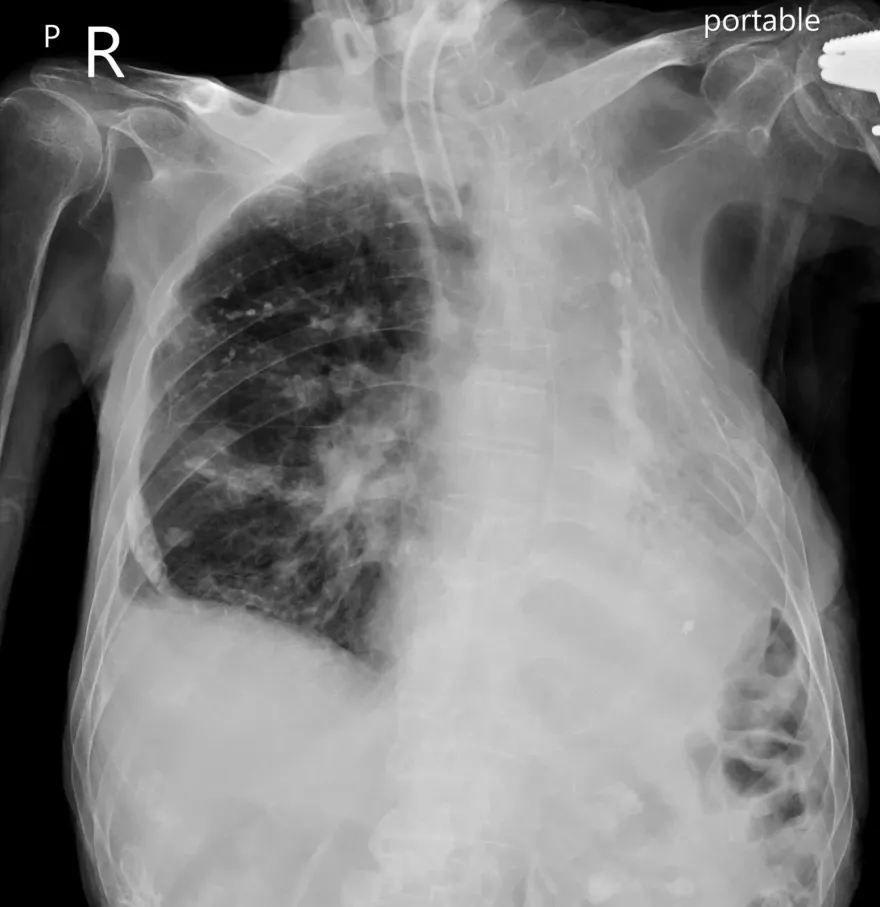

蘇一峰

肺結核

結核菌

打斷肋骨

肺部塌陷

胸腔內科